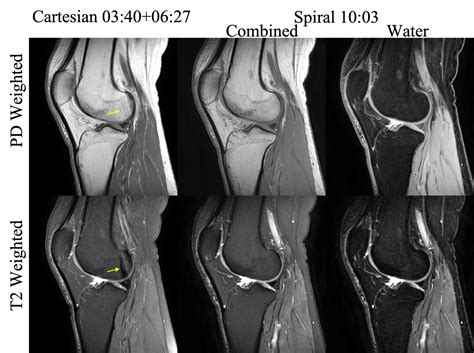

Understanding the significance of a Knee Normal MRI is crucial for anyone dealing with knee pain or injuries. Magnetic Resonance Imaging (MRI) is a powerful diagnostic tool that provides detailed images of the body's internal structures. When it comes to the knee, an MRI can reveal a wealth of information about the bones, cartilage, ligaments, and tendons, helping healthcare professionals make accurate diagnoses and develop effective treatment plans.

A Knee Normal MRI refers to an MRI scan of the knee that shows no abnormalities or signs of injury or disease. This type of scan is often used as a baseline for comparison when a patient presents with knee pain or suspected injury. By understanding what a normal knee MRI looks like, healthcare providers can more easily identify deviations from the norm, which may indicate issues such as tears, inflammation, or degenerative changes.

Interpreting a Knee Normal MRI

Interpreting a Knee Normal MRI involves looking at various structures within the knee to ensure they appear healthy. Key components to examine include:

• Detailed Images: MRI provides high-resolution images of soft tissues, bones, and other structures within the knee.